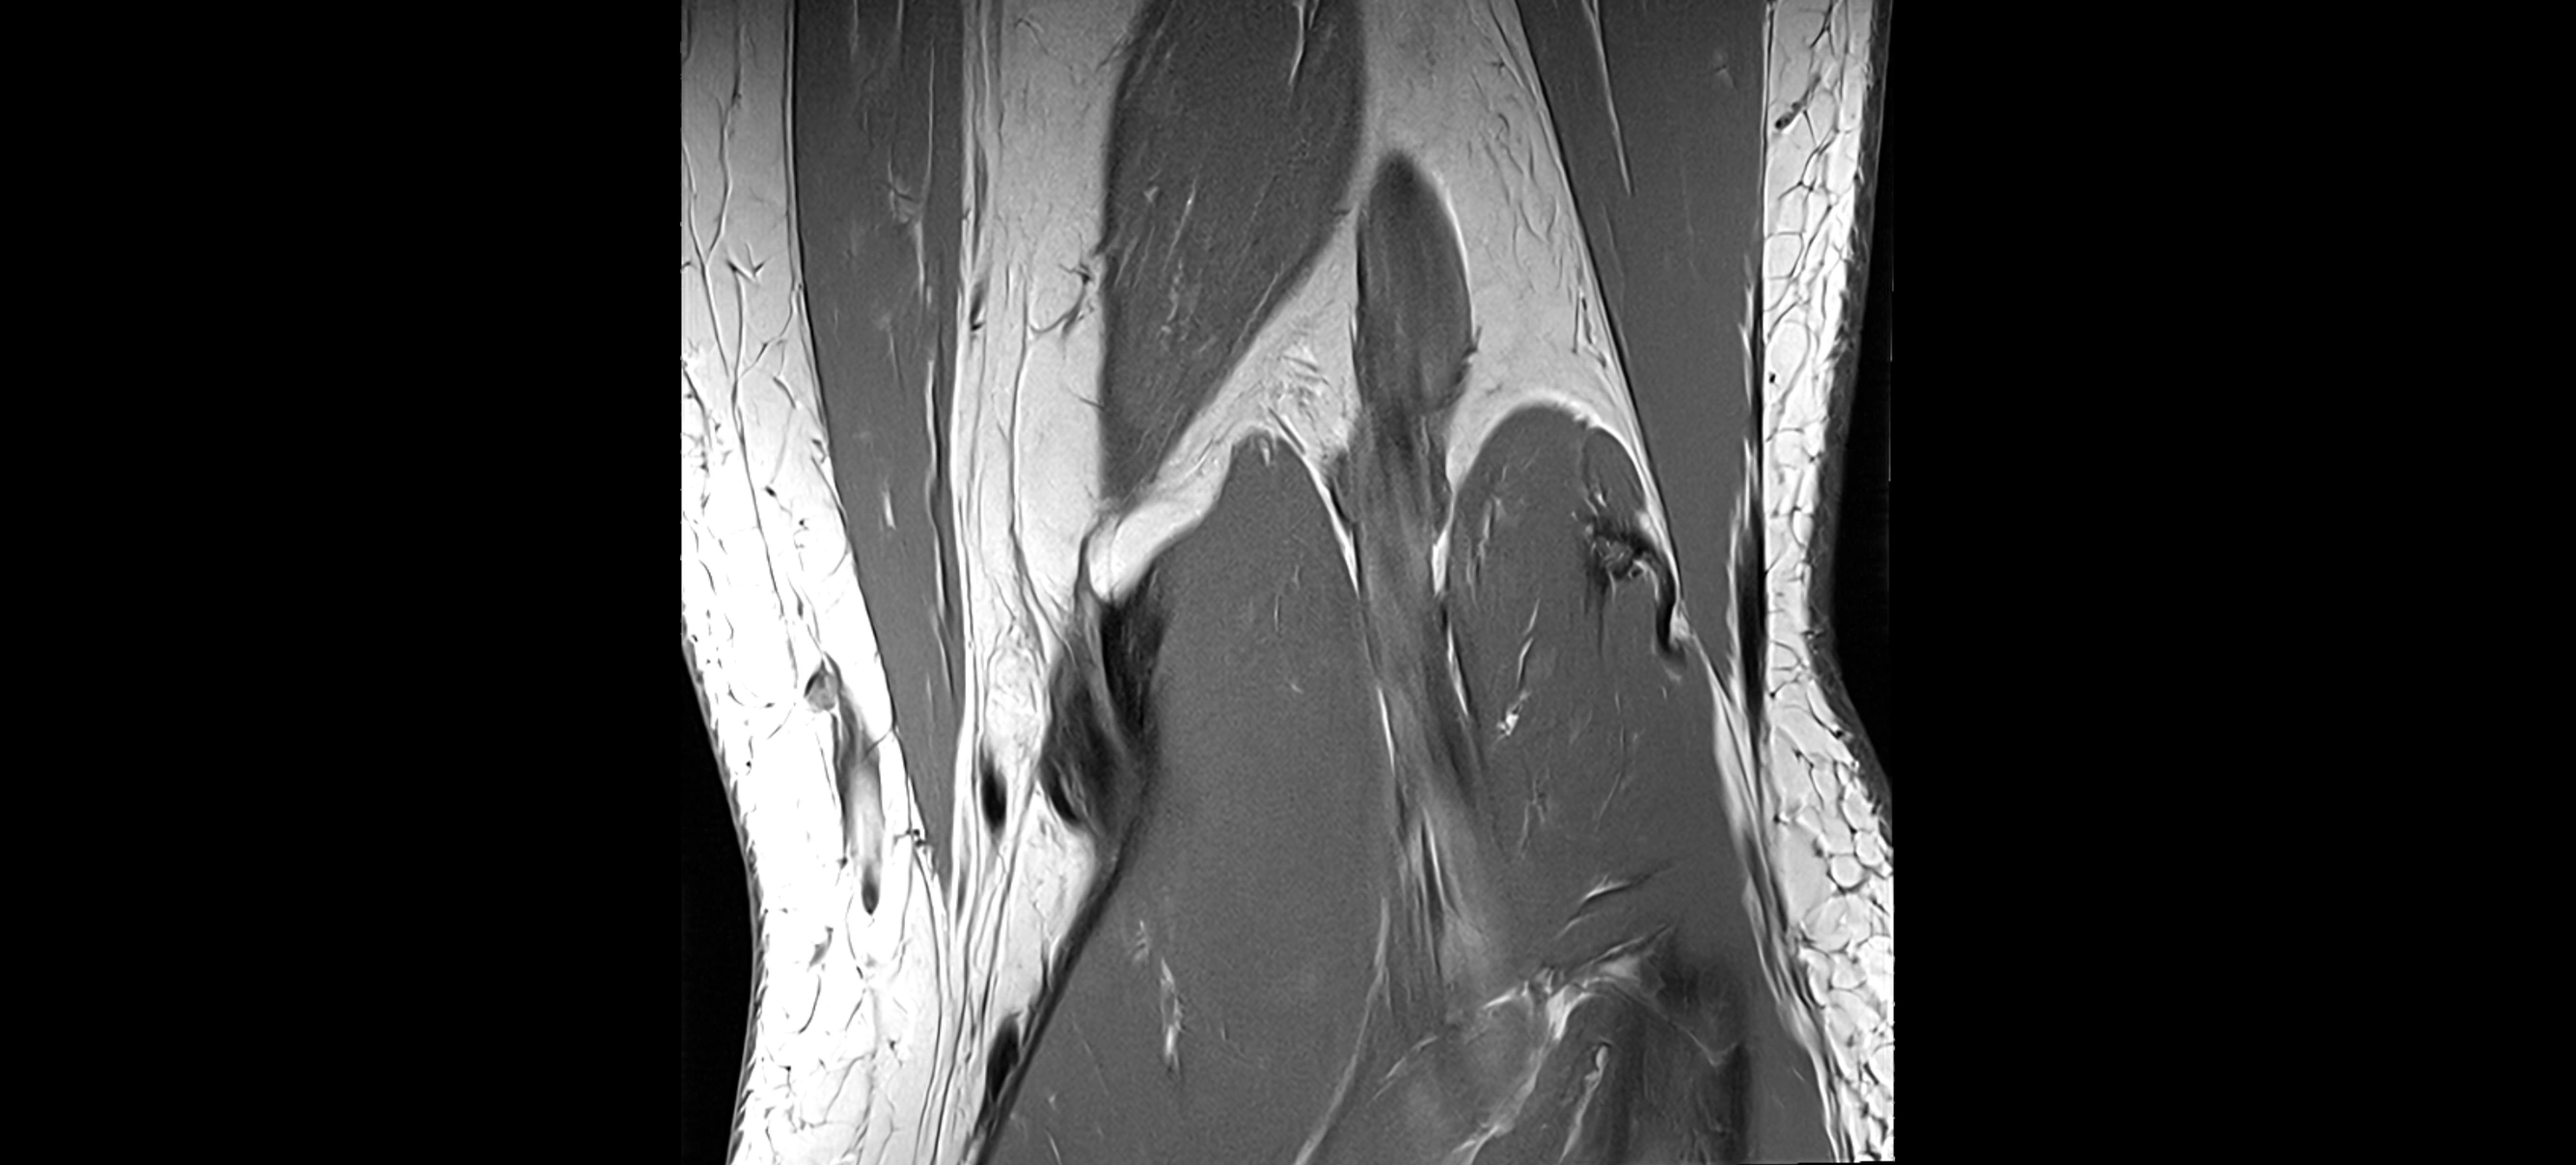

MRI Appearance

T2-weighted images:

• Normal ACL remains low signal

• Partial or complete tears appear as discontinuity, increased signal, or fiber laxity

STIR (Short Tau Inversion Recovery):

• Normal ACL shows dark low signal

• Acute injury shows bright hyperintensity due to edema and hemorrhage

Proton Density Fat-Saturated (PD FS):

• Normal ACL: dark, low-signal band

• Tears: bright intraligamentous hyperintensity, discontinuity, or abnormal course

MRI images

image